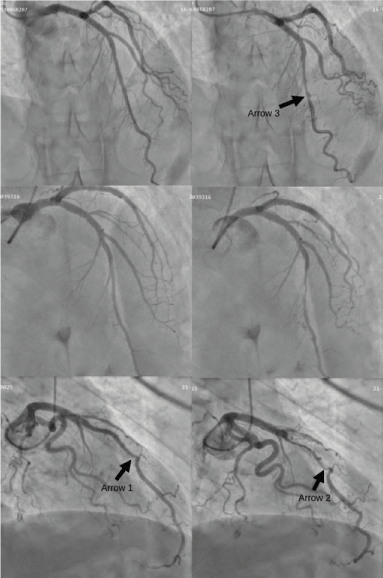

Figure 1. Left coronary angiography. Angiographies performed to CASE 1, (upper row, right oblique projection 10º /cranial projection 30º), CASE 2 (medium row, right oblique projection 15º /cranial projection 30º) and CASE 3 (lower row, right oblique projection 25º /cranial projection 10º) for diastole (left) and systole (right). The MB from case 3 presented milking effect even at the end of diastole (arrow 1) and kinking in the distal segment during systole (arrow 2). Partial coating of MB in case 1 (arrow 3).

Coronary Angiography and cCT Findings: Oligosymptomatic patients without treatment (case 1) or with betablocker treatment (case 2) revealed shorter lengths of MB on angiography than case 3 with refractory angina (Figure 1). Angiography also showed an inferior degree of systolic dynamic compression in cases 1 and 2 (34-39% basally compared to 72% in case 3). However, after NTGic, systolic dynamic compression was similar in all three cases (Figure 2).

In cases 1 and 2, the duration of absolute and relative DCC was shorter, mainly systolic. Nevertheless, for case 3, with a longer MB length (61 mm), the milking effect remained until the end of diastole (whole cycle) producing a compressive stenosis of greater severity (which resembled a fixed stenosis) (Table 2). In these severe cases, intracoronary imaging was important to identify other factors such as coronary spasm, endothelial dysfunction, and atherosclerotic disease that could explain the greater symptomatology of patient 3. In addition, case 3 presented marked distal kinking as it abruptly penetrated the interventricular sulcus, further increasing the resistance to flow. cCT confirmed greater length and depth of the MB in case 3 with a course very close to the right ventricle (Figure 3).